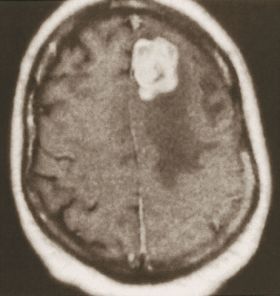

الشكل (2) صورة مرنان مغنطيسي للدماغ تظهر وجود ورم انتقالي دماغي (الكتلة البيضاء) وحولها تظهر منطقة الوذمة الدماغية (ناقصة الإشارة أو «سوداء»).

إن الوذمة في (الشكل 2) موضعة في منطقة محدودة من الدماغ حول الكتلة الورمية، أما في حال كون الوذمة الدماغية معممة فعندها تُظهر الصور الدماغية إمحاء في الأثلام وأحياناً صِغراً في حجم البطينات الدماغية نتيجة انتباج النسيج الدماغي.